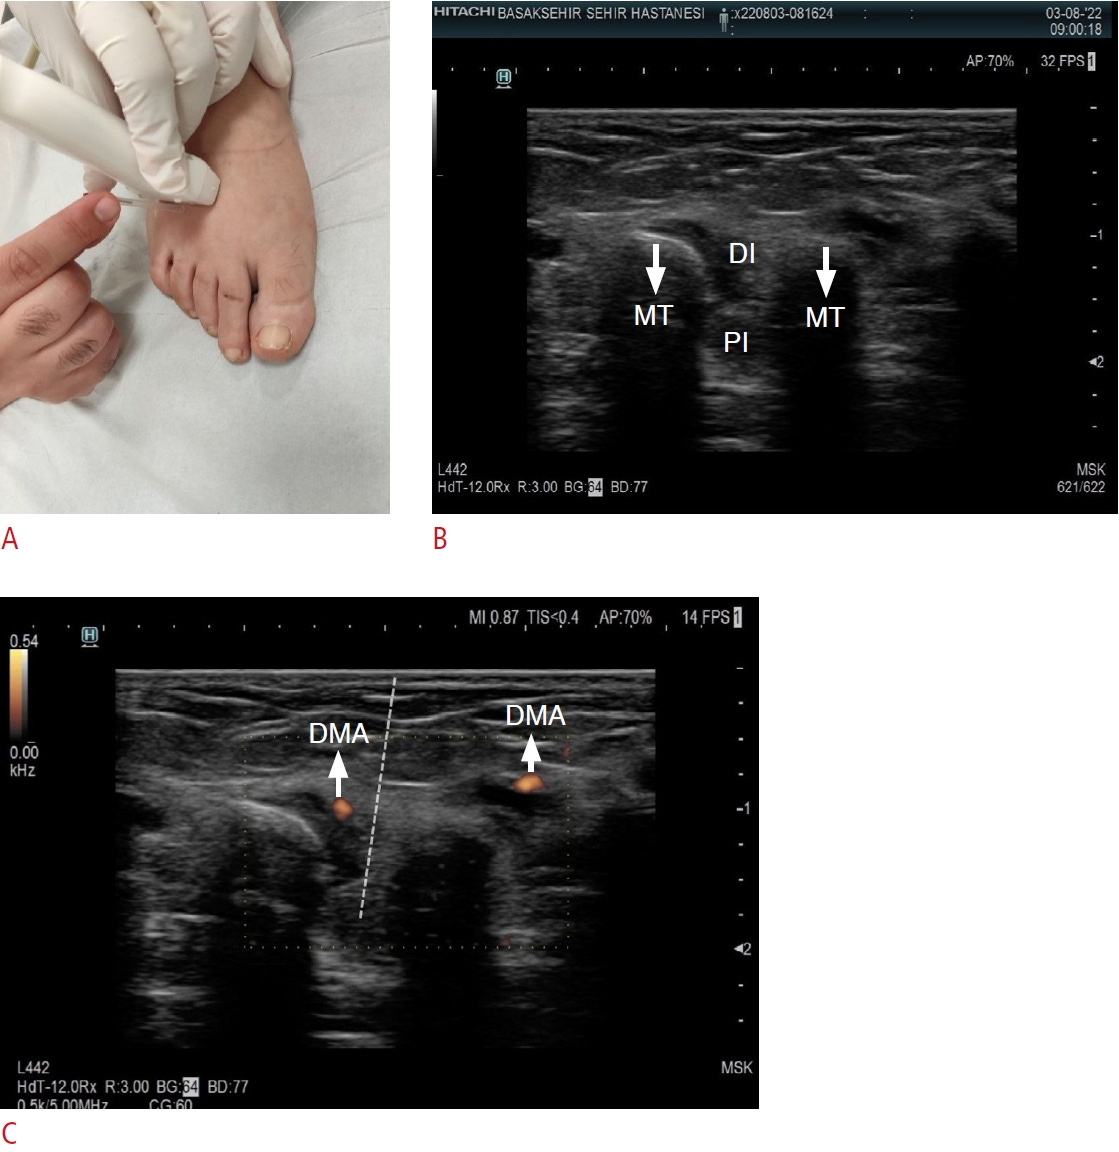

Guía ecográfica para el tratamiento del punto gatillo del músculo interóseo.

A. En el abordaje guiado por ecografía, el transductor se coloca y la punción se realiza en la posición adecuada.

B. Se visualizan los huesos metatarsianos y los músculos interóseos.

C. Se identifican las arterias metatarsianas dorsales, que se evitan durante el procedimiento.

MT: hueso metatarsiano; DI: músculo interóseo dorsal; PI: músculo interóseo dorsal; DMA: arteria metatarsiana dorsal.